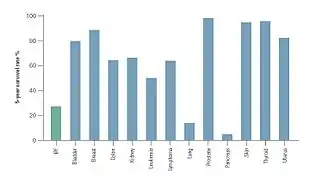

The clinical course of IPF can be unpredictable.[3][65][66] IPF progression is associated with an estimated median survival time of 2 to 5 years following diagnosis.[1][3] The 5-year survival for IPF ranges between 20 and 40%,[66] a mortality rate higher than that of a number of malignancies, including colon cancer, multiple myeloma and bladder cancer.[65][66]